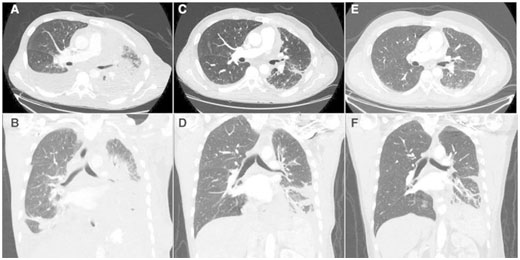

三周后,疼痛癥狀消失,告別吸氧、可以暢快呼吸,并且,全身腫瘤縮少46%,胸壁病灶不見,腦轉(zhuǎn)移瘤大部分消退;5個月后,癥狀不斷改善,全身腫瘤縮小77%,腦轉(zhuǎn)移灶完全消失!

◆第26天(C,D)和第155天(E,F)胸部圖像,腫瘤縮小77%!